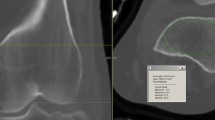

In cases of severe calf trauma, such as tibial diaphyseal fractures, the anterior compartment is most frequently affected [8], so we measured and recorded the ICP in the anterior compartment immediately upon each patient’s arrival at the emergency room. A 22-gauge intravenous catheter filled with normal saline was inserted into the anterior compartment of the affected limb and connected to an invasive arterial blood pressure monitor system (IABPMS) to measure and monitor the ICP continuously for 48 h. The patient’s ICP and blood pressure were recorded by nurses each hour [19,20,21,22] (Fig. 2).

Based on these records, we identified the maximum ICP and the minimum ΔP, which is a widely recognized indicator of skeletal muscle perfusion [21]. An ICP elevation of above 30 mmHg is considered clinically significant [5,6,7]. In order to determine the duration of ICP elevation based on continuous monitoring, the accumulated ICP was calculated as the sum of hourly ICP values exceeding 30 mmHg. However, simply adding ΔP values together is meaningless, because the smaller the ΔP, the more severe the obstruction of the blood circulation in the affected limb. According to a previous study, the diastolic blood pressure of patients increased drastically due to stress and pain after lower extremity injury, but gradually decreased with analgesia, immobilization, and hemorrhage, culminating in a mean diastolic blood pressure of about 80 mmHg 48 h after injury [19]. Since an ICP elevation > 30 mmHg was considered clinically significant and ΔP = diastolic blood pressure minus ICP, we determined a reference value of 50 mmHg. We then summed all of the hourly ΔP values below 50 mmHg (Fig. 3).